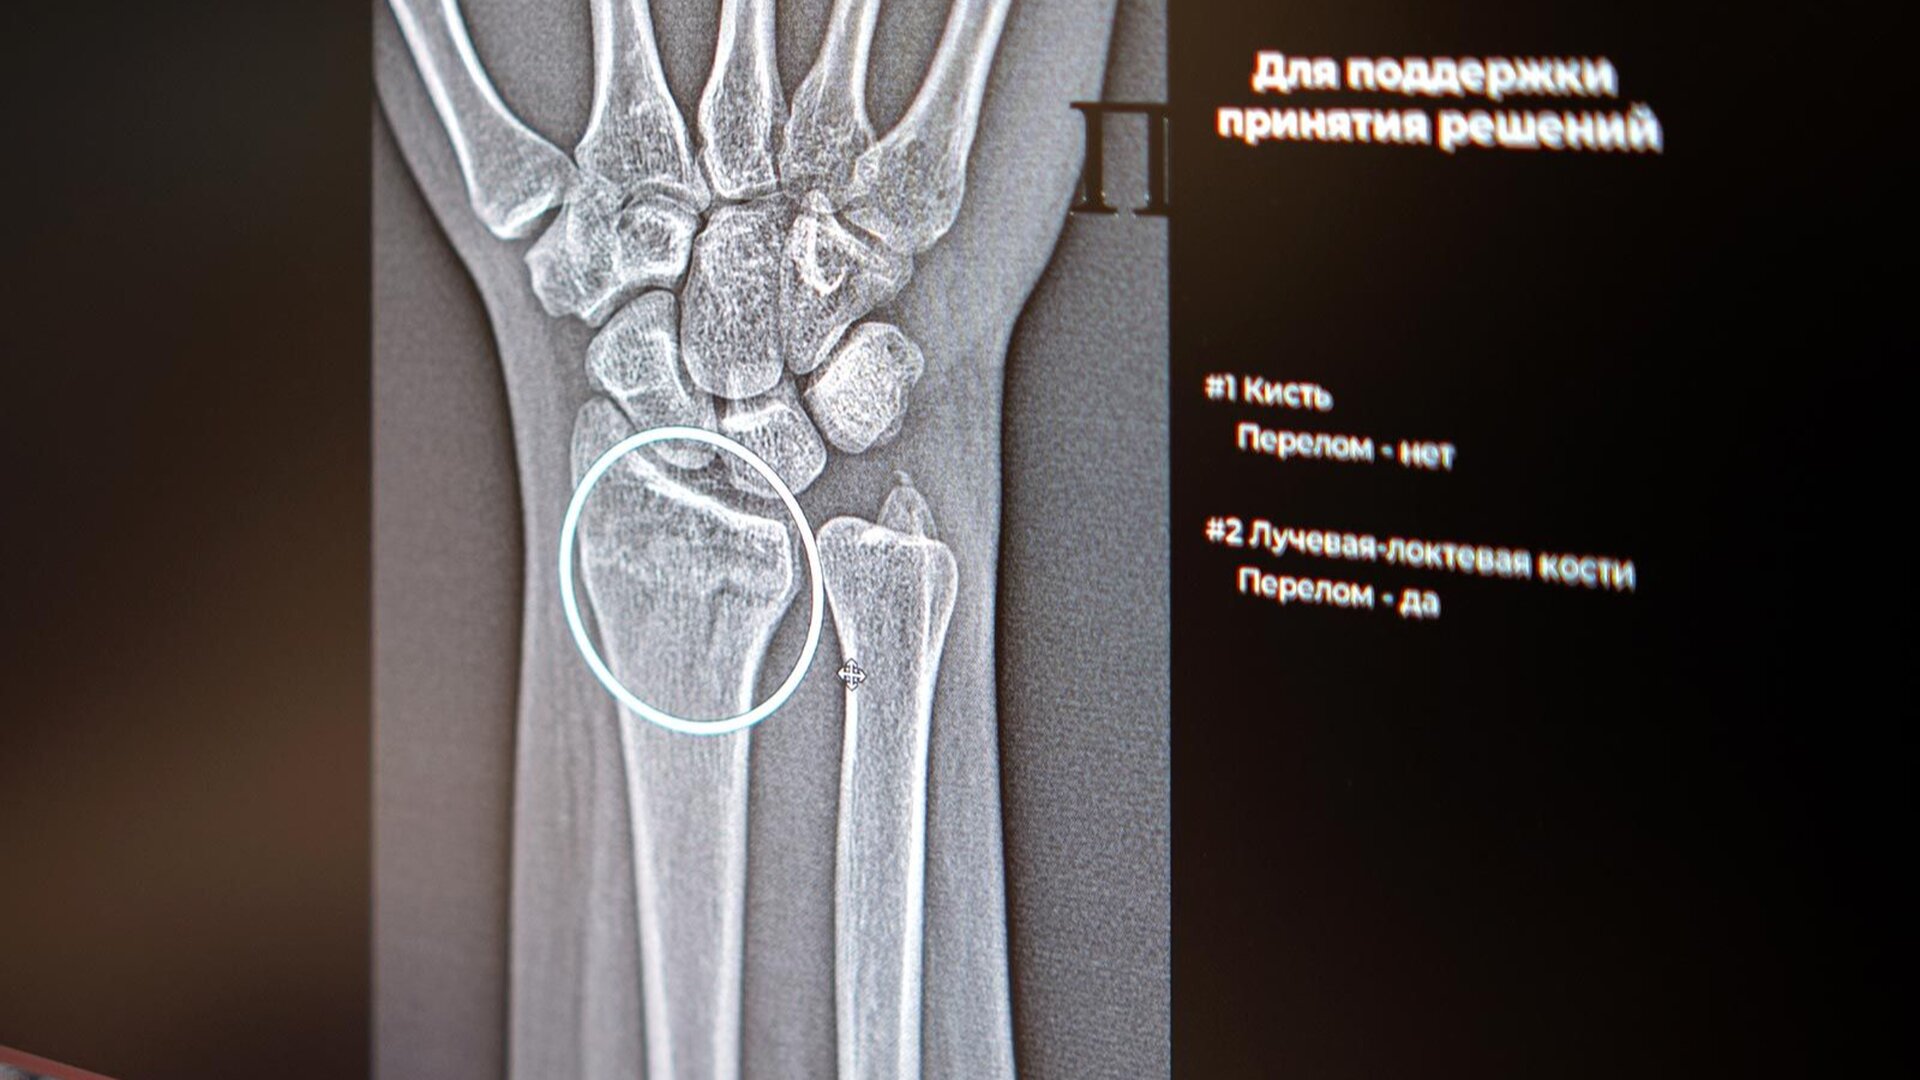

Столичные врачи получили в распоряжение два новых сервиса на основе искусственного интеллекта, которые помогают точнее диагностировать сложные переломы голеностопного и лучезапястного суставов.

Цифровые ассистенты анализируют рентгеновские снимки и автоматически отмечают повреждённые участки, даже если на изображении видны признаки сразу нескольких переломов. Как отметила заместитель Мэра Москвы по вопросам социального развития Анастасия Ракова: «Цифровые решения уже более пяти лет помогают столичным рентгенологам — прежде всего, в анализе медицинских снимков. Недавно мы запустили два новых ИИ-сервиса, которые помогают обнаруживать на рентгеновских изображениях травмы костей голеностопного и лучезапястного суставов — одних из самых функциональных и при этом уязвимых».

Алгоритмы не только отличают норму от патологии, но и выполняют точные измерения границ и размеров повреждений. Особенно ценно, что искусственный интеллект способен заметить даже минимальные трещины, которые могут ускользнуть от человеческого глаза.«Травмы предплечья, кисти и голени встречаются достаточно часто. Диагностика перелома включает осмотр травматолога с последующим выполнением рентгенографии. Специалисты используют ИИ-алгоритм как инструмент, способный повысить точность и скорость анализа лучевого изображения, что критически важно для постановки диагноза», — пояснил главный внештатный специалист по лучевой и инструментальной диагностике Москвы Юрий Васильев.